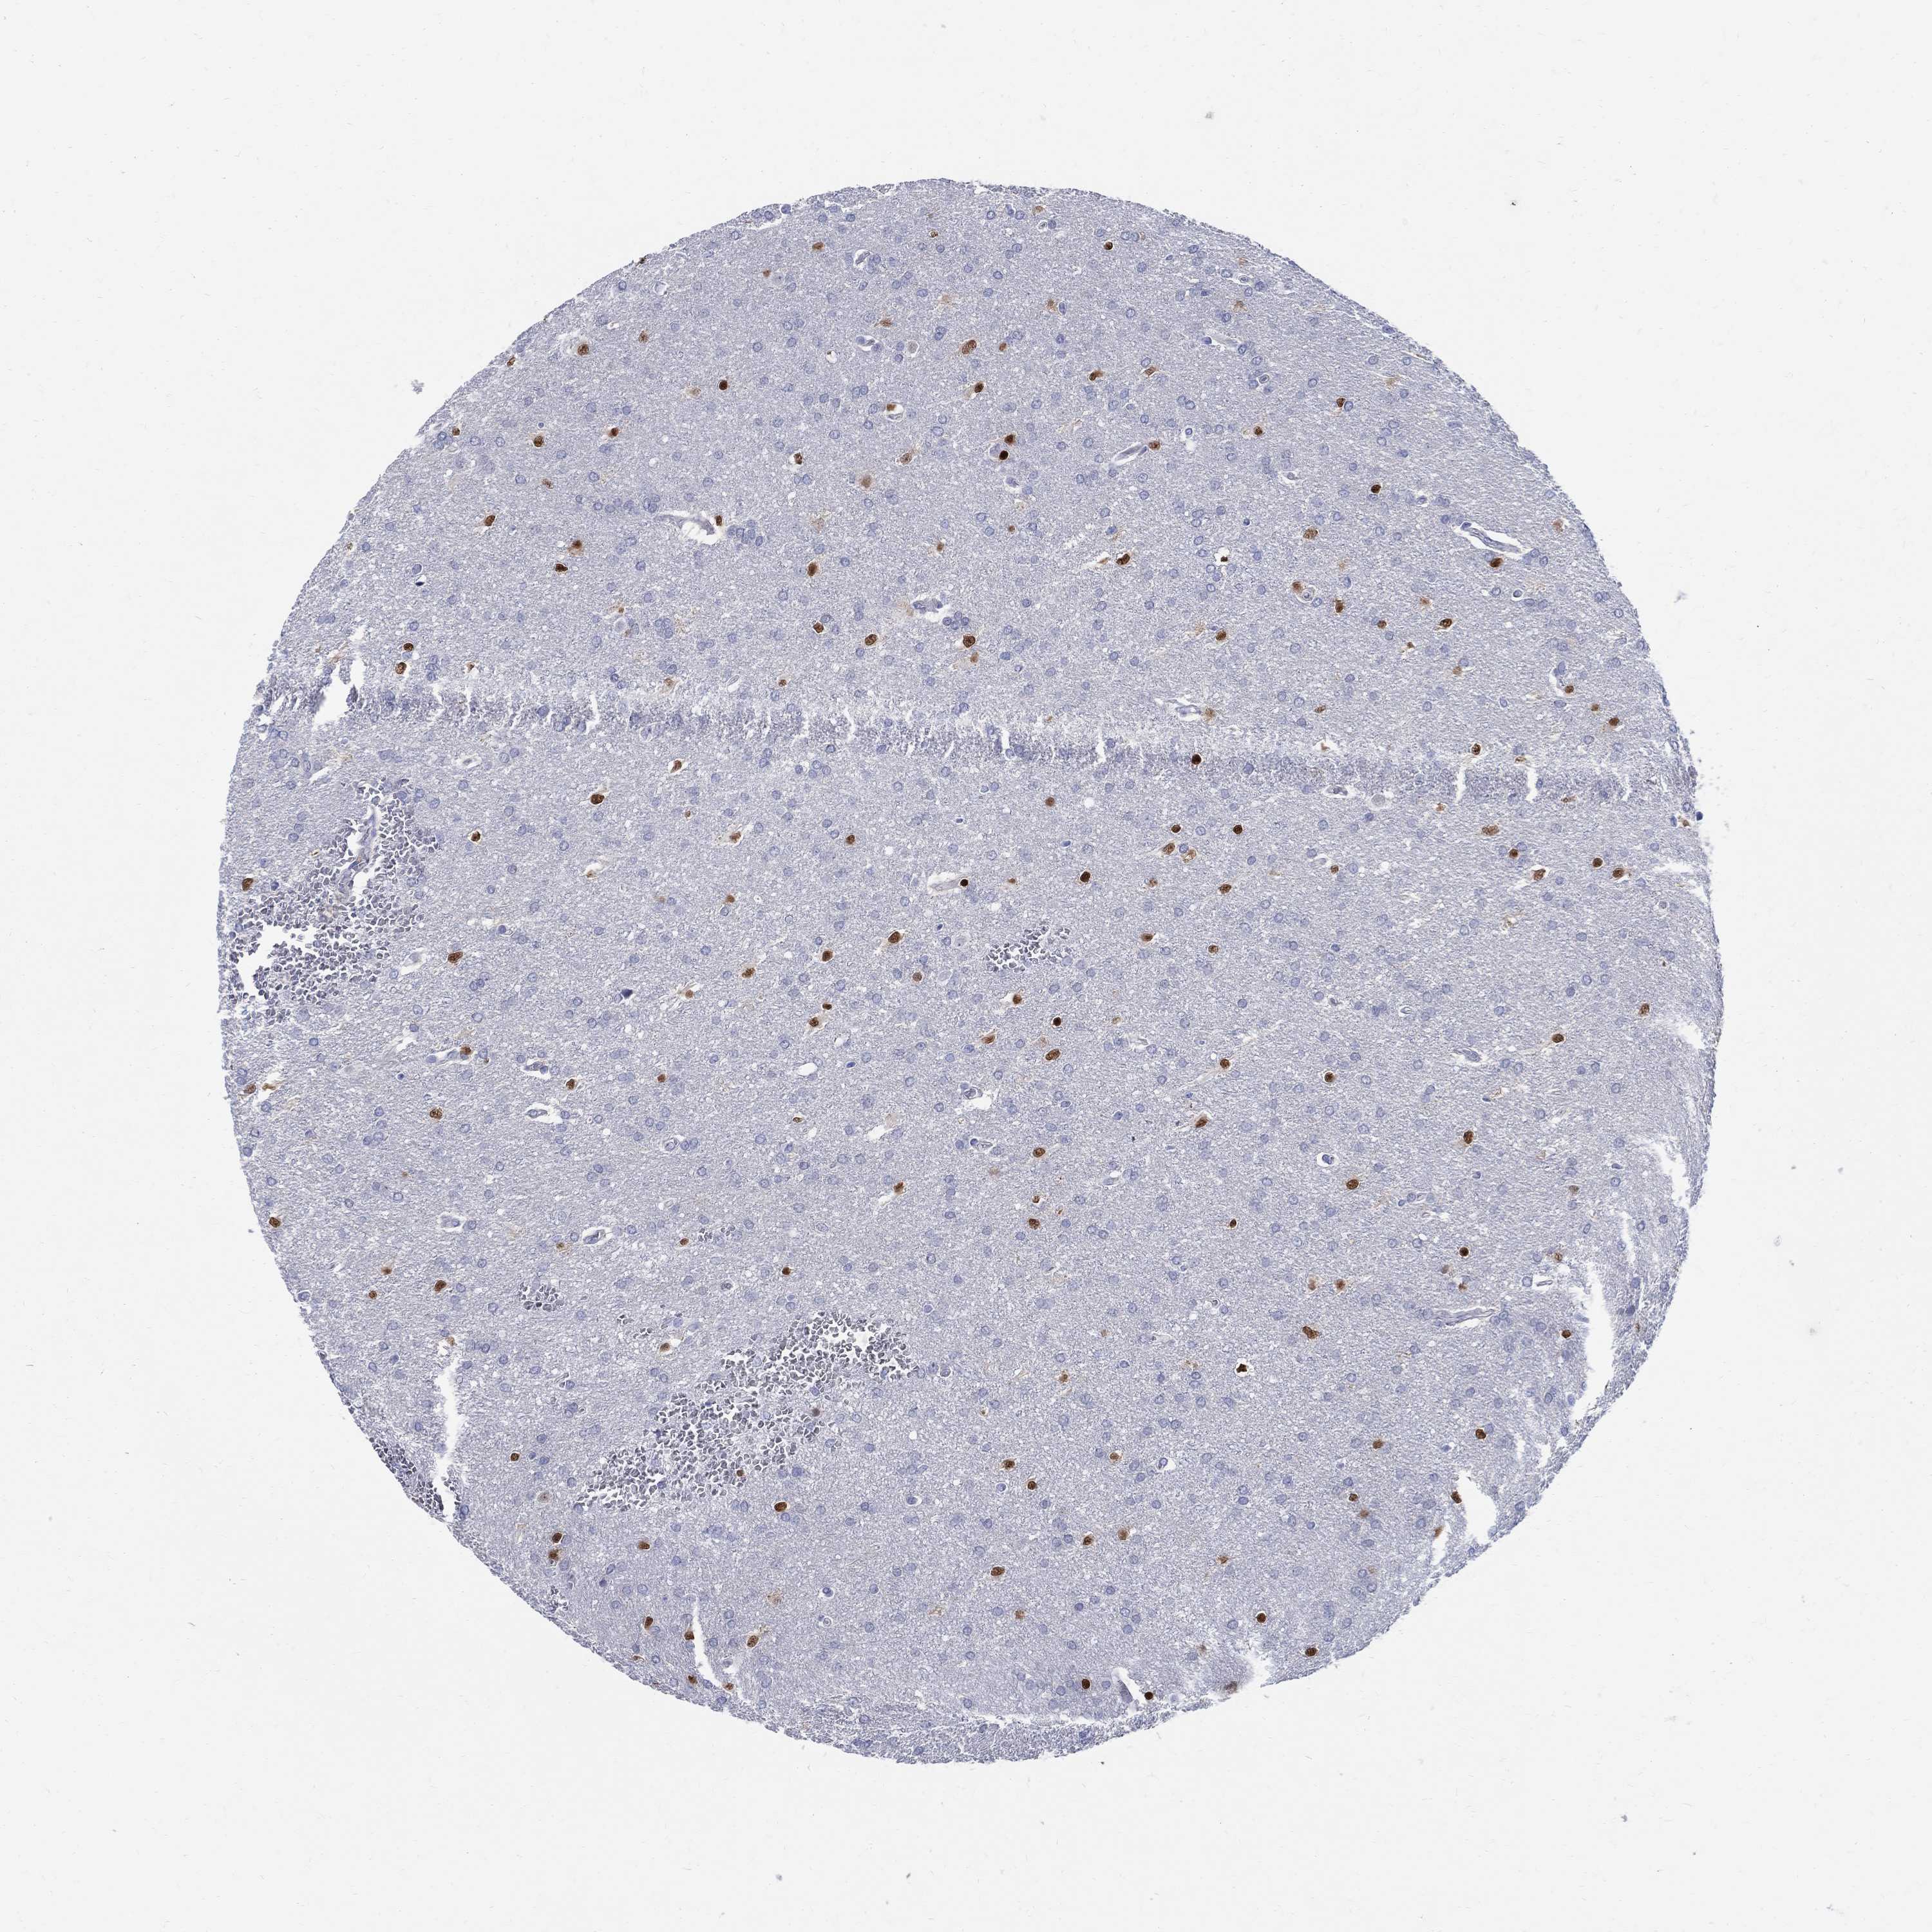

GLIOMA - Protein expressioni

A mouse-over function shows sample information and annotation data. Click on an image to view it in a full screen mode. Samples can be filtered based on level of antibody staining by selecting one or several of the following categories: high, medium, low and not detected. The assay and annotation is described here.

Note that samples used for immunohistochemistry by the Human Protein Atlas do not correspond to samples in the TCGA dataset.

Antibody stainingi

Antibody staining in the annotated cell types in the current human tissue is reported as not detected, low, medium, or high, based on conventional immunohistochemistry profiling in selected tissues. This score is based on the combination of the staining intensity and fraction of stained cells.

Each image is clickable and will lead to virtual microscopy that enables deeper exploration of all samples and also displays staining intensity scores, fraction scores and subcellular localization as well as patient and tissue information for each sample.

Antibody HPA045725

Antibody CAB079745

Staining

High

Medium

Low

Not detected

Intensity

Strong

Moderate

Weak

Negative

Quantity

>75%

75%-25%

<25%

None

Location

Nuclear

Cytoplasmic/membranous

Cytoplasmic/membranous,nuclear

Glioma, malignant, Low grade

Glioma, malignant, High grade